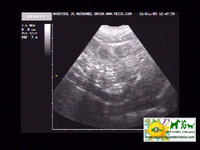

ecografía donde se aprecian las neoplasias hepáticas |

video de ecografía sin doppler: |